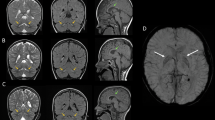

Variants in the WD repeat 45 (WDR45) gene in human Xp11.23 have recently been identified in patients suffering from neurodegeneration with brain iron accumulation, a genetically and phenotypically heterogeneous condition. WDR45 variants cause a childhood-onset encephalopathy accompanied by neurodegeneration in adulthood and iron accumulation in the basal ganglia. They have been almost exclusively found in females, and male lethality was suggested. Here we describe a male patient suffering from a severe and early neurological phenotype, initially presenting early-onset epileptic spasms in clusters associated with an abnormal interictal electroencephalography showing slow background activity, large amplitude asynchronous spikes and abnormal neurological development. This patient is a carrier of a 19.9-kb microdeletion in Xp11.23 containing three genes, including WDR45. These findings reveal that males with WDR45 deletions are viable, and can present with early-onset epileptic encephalopathy without brain iron accumulation.